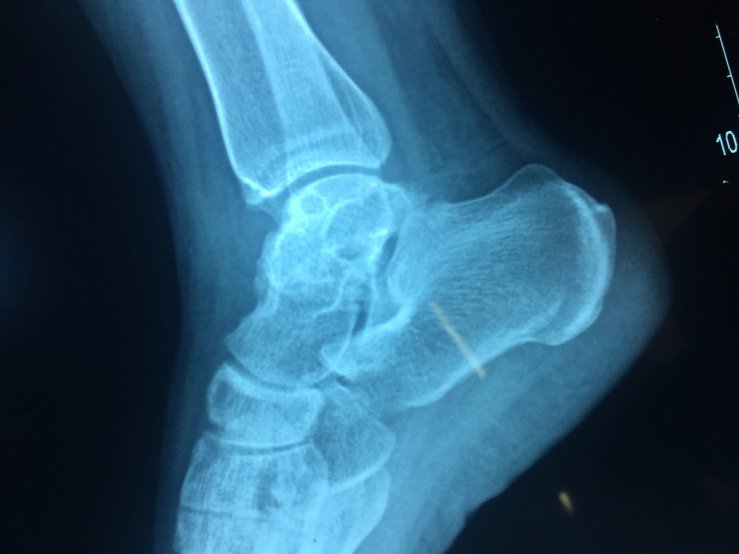

Còn bài thuốc đắp điều trị bệnh gãy xương, thoát vị đĩa đệm cũng được bào chế từ thảo dược tự nhiên có dược tính mạnh, để dưới dạng bột khô. Lúc dùng cho ra bát, chế với rượu trắng thành hồ rồi đắp lên vị trí bị tổn thương. Trước khi đắp thuốc cần xoa bóp bằng thuốc nước. Thuốc sẽ ngấm và giúp lành xương chỉ sau một vài tiếng nhưng có những người phải mất tới 2 -3 ngày mới có hiệu quả”.

Thuốc được đắp trực tiếp lên vị trí bị gãy